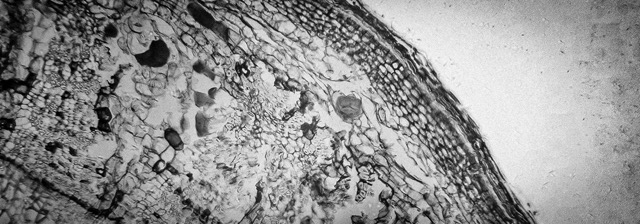

메디컬 적인 관리 이후 피부 셀룰라는 매우 빠르게 생장과 분화를 반복합니다. 사람의 피부조직은 생각보다 매우 유기적이고 예민하며 놀라울 정도로 체계적이기 때문에 관리방법, 심리상태 , 컨디션에 따라 결과가 다르게 나타날 수 있으므로 메디컬 관리 이후의 자가관리는 아주 중요합니다.

피부가 자극을 받으면 우리 피부는 <응급상황> 상태로 돌입되는데, 어떻게 보면 외부로 부터 전쟁을 선포받은 입장인거죠. 그래서 우리 피부는 "세포 더 빨리 만들어!", "콜라겐 생산량 늘려!", "염증 빨리 진화 시켜!", "새 혈관도 튼튼하게 만들어!" 라고 바삐 움직이는 거랍니다. EGF는 이러한 것들을 지시하고, 대답할 수 있는 성분으로 피부 속 EGF가 부족하면 이러한 일련의 과정들에 브레이크가 걸리는 거죠. 그래서 회복이 더디고 재생이 원활하지 않고, 시술 후 자극이 빨리 사라지지 않는거랍니다.

시술을 받으면 우리 피부는 즉시 '복구모드'로 전환됩니다. 이때 피부 세포들이 가장 먼저 찾는게 EGF고, 공사 현장에 비유하자면 EGF가 현장감독 같은 역할을 한다고 생각하시면 됩니다 :) EGF가 피부에 도착하면 먼저 손상된 세포들의 EGF 수용체가 결합해서 "빠르게 회복 작업 시작해라!" 라고 명령을 내립니다. 그러면 평소보다 더 빠른 속도로 새로운 피부 세포들이 만들어지기 시작하죠.